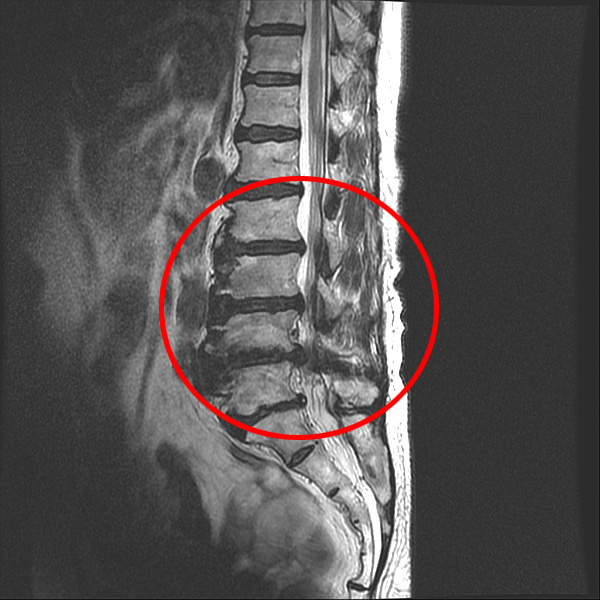

척추관협착증 환자의 MRI

앞서 유합술을 하게 되면, 뼈가 유합된 위아래 마디가 가장 큰 스트레스를 받는다고 설명 드렸습니다. 만약 인접한 마디가 젊고 건강하다면 움직임이나 충격을 받아도 당분간은 그리 큰 문제가 되지 않겠지만, 유합술을 받는 주변 부위의 퇴행이 이미 심하다면 그 유합된 부위로부터 넘어오는 스트레스나 압력을 견디지 못할 것입니다.

협착증은 여러 레벨에 걸쳐 퇴행이 진행된 상태이기 때문에 어느 특정 부위를 유합한다 해도 이미 퇴행되어 약해진 위아래 인접 마디가 움직임이나 충격을 견디기가 힘이 들 것입니다. 그래서 협착증 환자는 수술 이전에 유합술 이후 생길 수 있는 인접분절질환에 대해 충분히 알고 있어야 하며, 척추협착증수술을 진행하는 병원 역시 환자에게 수술 이후 인접분절질환의 발생 가능성과 예방법에 대해 철저히 교육해줄 필요가 있습니다.